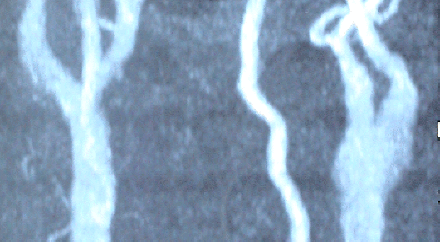

The patient was sent for another investigation. MRA showed complete occlusion of the left ICA and partial of the proximal segment of the ECA.

Check MRA performed 16-July-2006 showing the patency and established circulation 1 month after the operation.